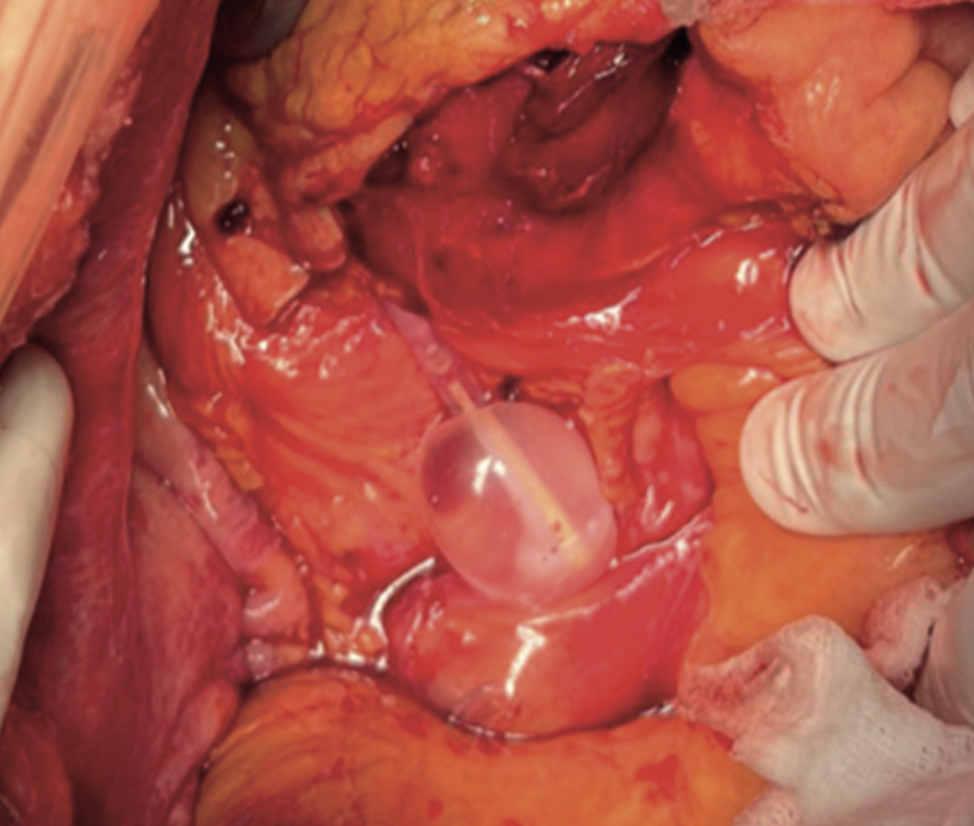

Retroneumoperitoneo secundario a rotura ureteral iatrogénica por sondaje vesical.

Se presenta el caso de una mujer de 83 años que acude al servicio de Urgencias con clínica de obstrucción inestinal secundaria a neoplasia de colon ascendente, que se interviene de forma urgente evidenciándose intraoperatoriamente perforación ureteral por sondaje vesical traumático.